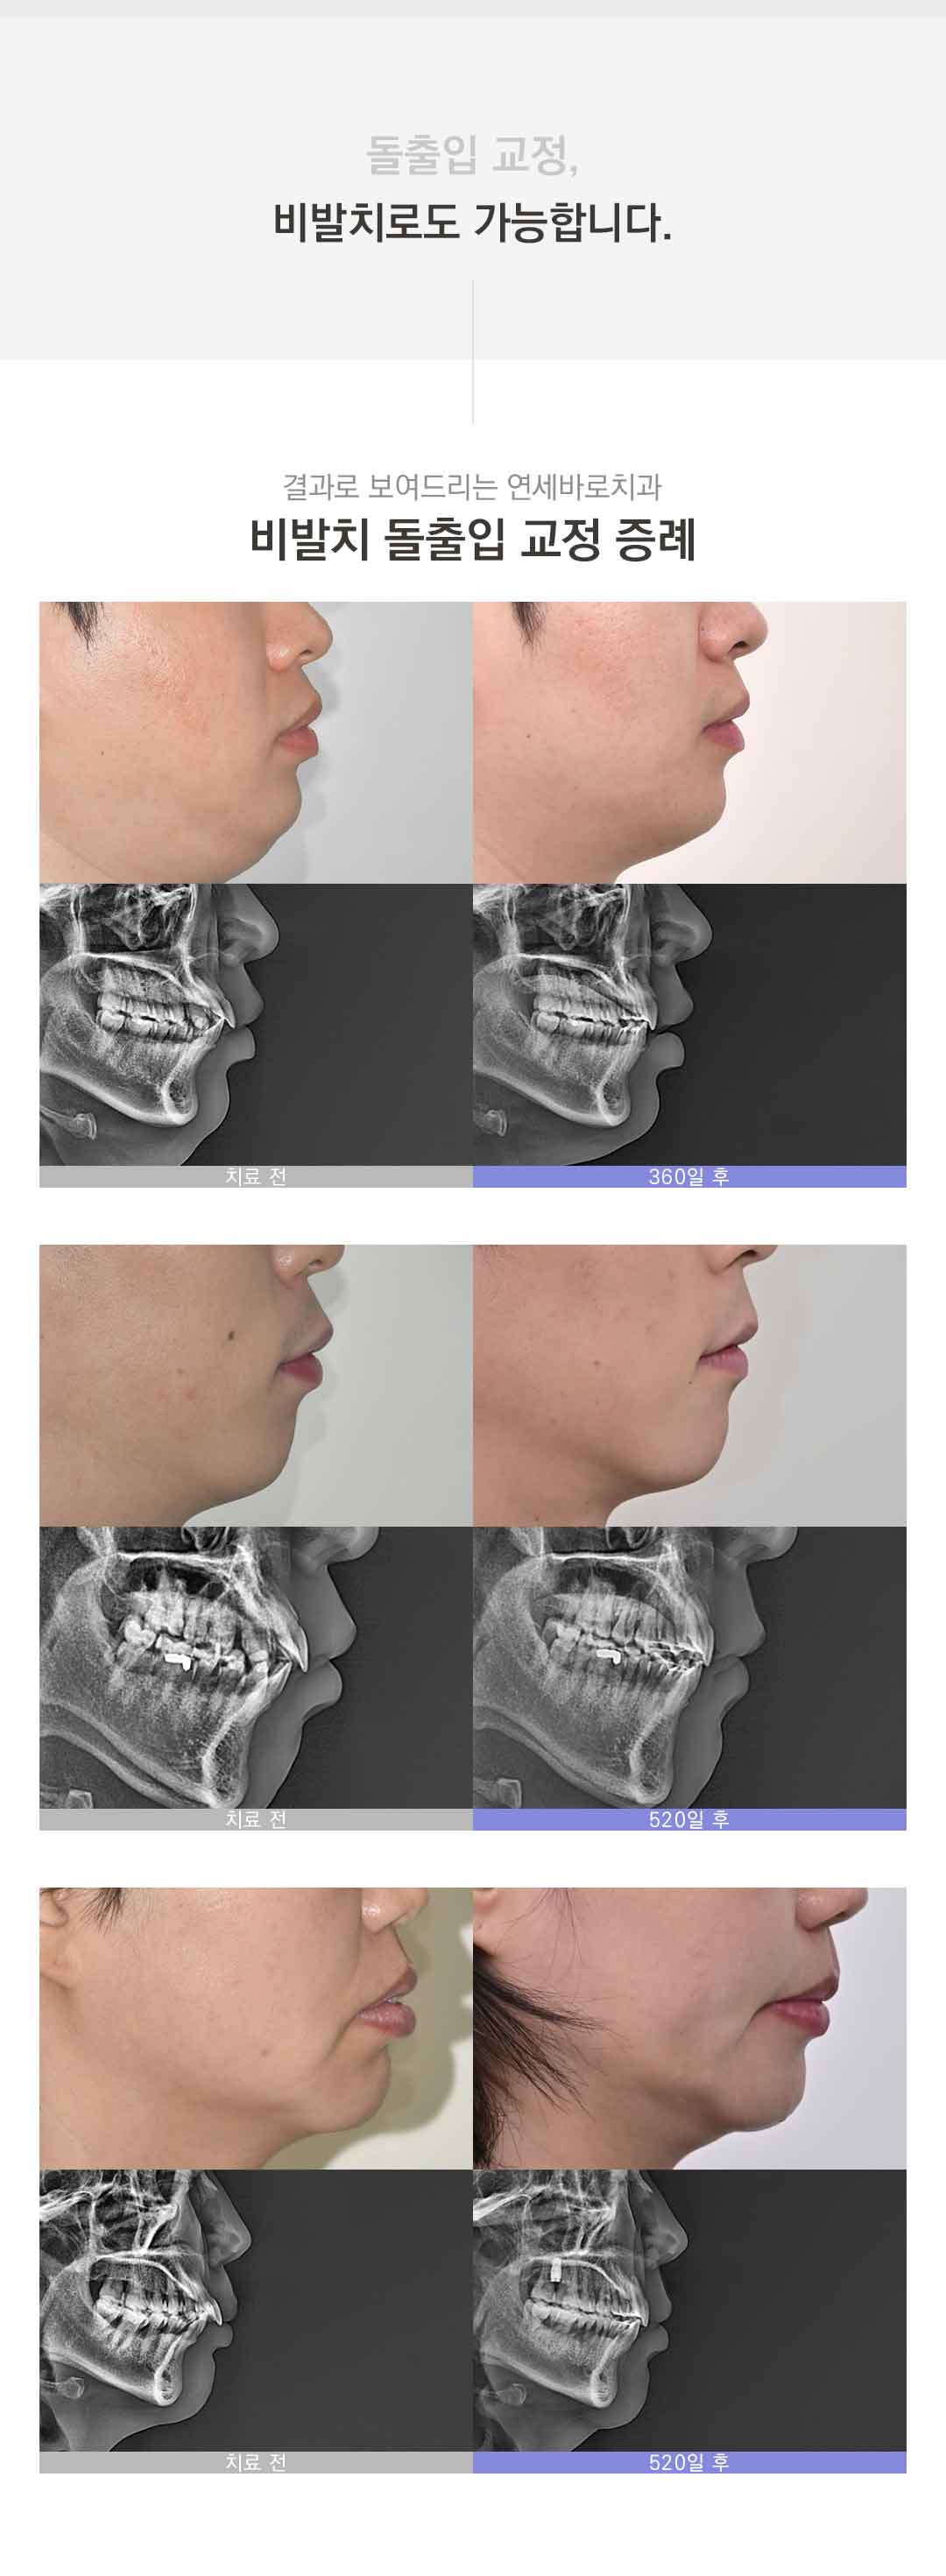

돌출입 교정

치아교정에는 충치 및 치주질환, 턱관절문제 등 다양한 부작용의 가능성이 존재합니다. 원장님과의 상담 후 치료여부를 결정하시길 바랍니다